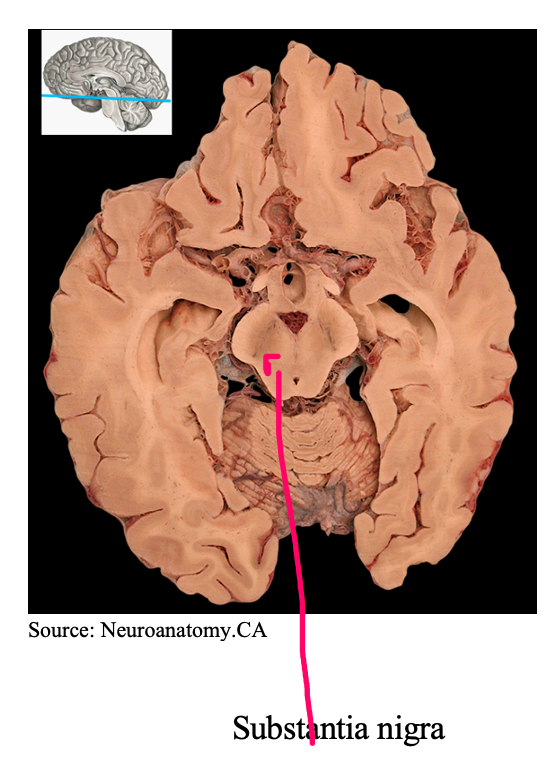

What is the structure called highlighted in red

Substantia nigra